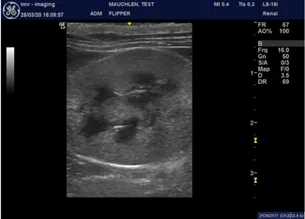

Feline left kidney using a linear hockey stick probe

• Superficial abdominal structures (especially in cats) – SI and Kidney.